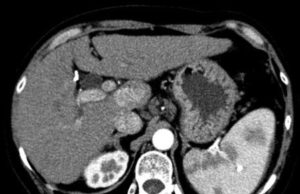

Intra-arterial hepatocellular carcinoma treatment at the dawn of systemic therapy

Bruno Sangro, director of the Liver Unit and co-director, of the HPB Oncology Area, Clinca Universidad de Navarra, Pamplona, Spain, delivered the European Conference on Interventional Oncology (ECIO) Honorary Lecture on the topic ‰ÛÏIntra-arterial treatment of hepatocellular carcinoma (HCC) at the dawn of systemic therapy‰Û.